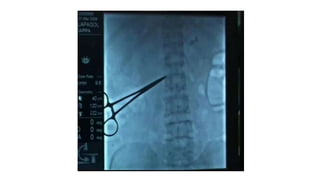

This document discusses various pain management techniques including stellate ganglion block, celiac plexus block using fluoroscopic imaging, and paravertebral nerve block. It also mentions subarachnoid phenol in glycerine dorsal rhizotomy, subarachnoid absolute alcohol, superior hypogastric block, and ganglion impar block. References are provided from publications in 1997, 2005, 1990, and 1997 on these techniques.